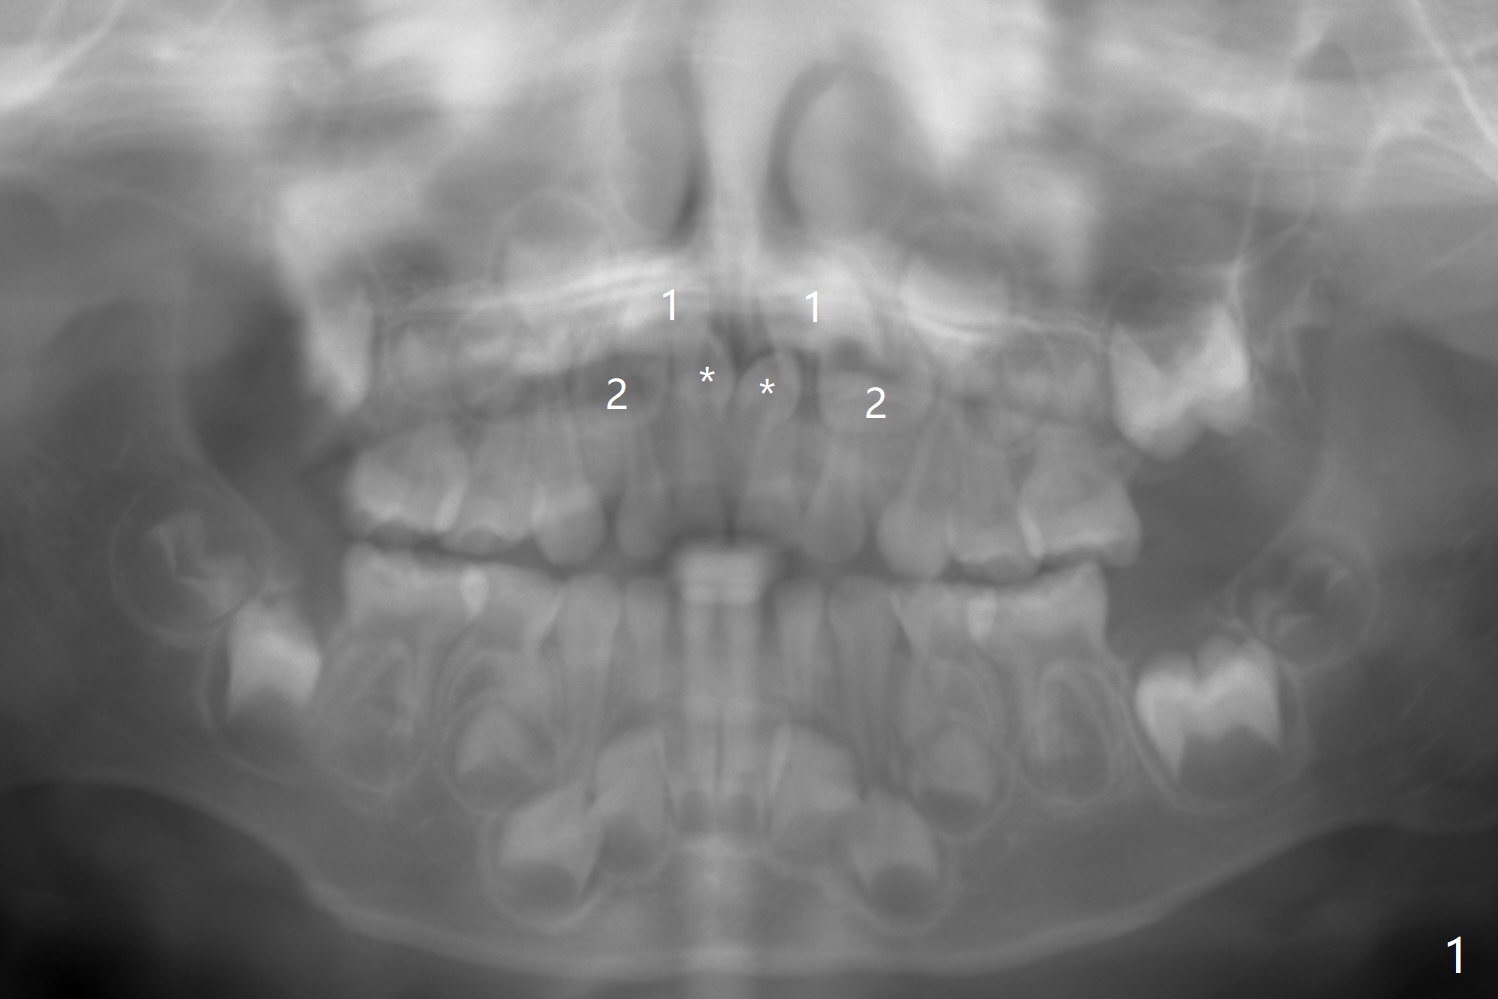

A 3-year-old boy with attention deficit and autism has several incipient caries.  Panoramic X-ray reveals that two of mesiodens (Fig.1 *) block eruption of the upper central incisors (1), as compared to the lateral ones (2).  When is the best time to extract the mesiodens?

PA is taken 10 months later (Fig.5).  The roots of the supernumerary teeth (*) elongate, while the permanent centrals (1) have descended as the same level as the laterals (2).  The divergent centrals seem not be able to cause root resorption of the deciduous ones.  The parents have hesitated to accept surgical removal.  This PA (Fig.6) is taken 6 months later (as compared to Fig.5).  The apices of the supernumerary teeth (*) appear to have closed, while the permanent centrals (1) remain as the same level as the laterals (2).  The divergent centrals seem not be able to cause root resorption of the deciduous ones.  The patient is superactive.